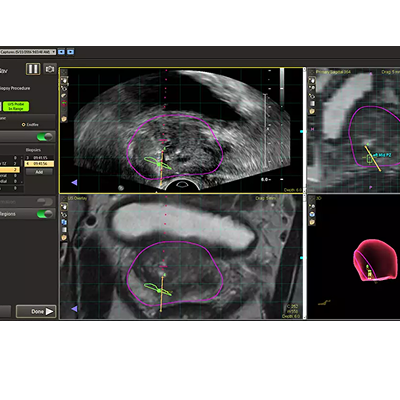

放射科使用 DynaCAD Prostate 定义前列腺边界和目标后,DynaCAD 泌尿科会显示结果信息以供泌尿科检查。专用工具允许您根据需要编辑前列腺分割,并根据先前的活检程序核心位置添加目标。这为使用飞利浦 UroNav 的融合引导活检创建了一个即用型计划。

DynaCAD Urology 允许用户导出未加密的 T2 MR 图像、腺体和目标分割以及活检核心位置,以用于外部治疗计划和治疗系统。从 DynaCAD Urology 导出这些数据,无需放射科医生为活检和治疗目的分别分割腺体和靶标,从而简化了整个工作流程。